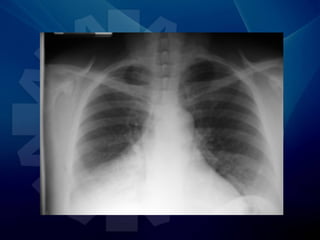

• Radiografía de tórax

• Rx de Tórax